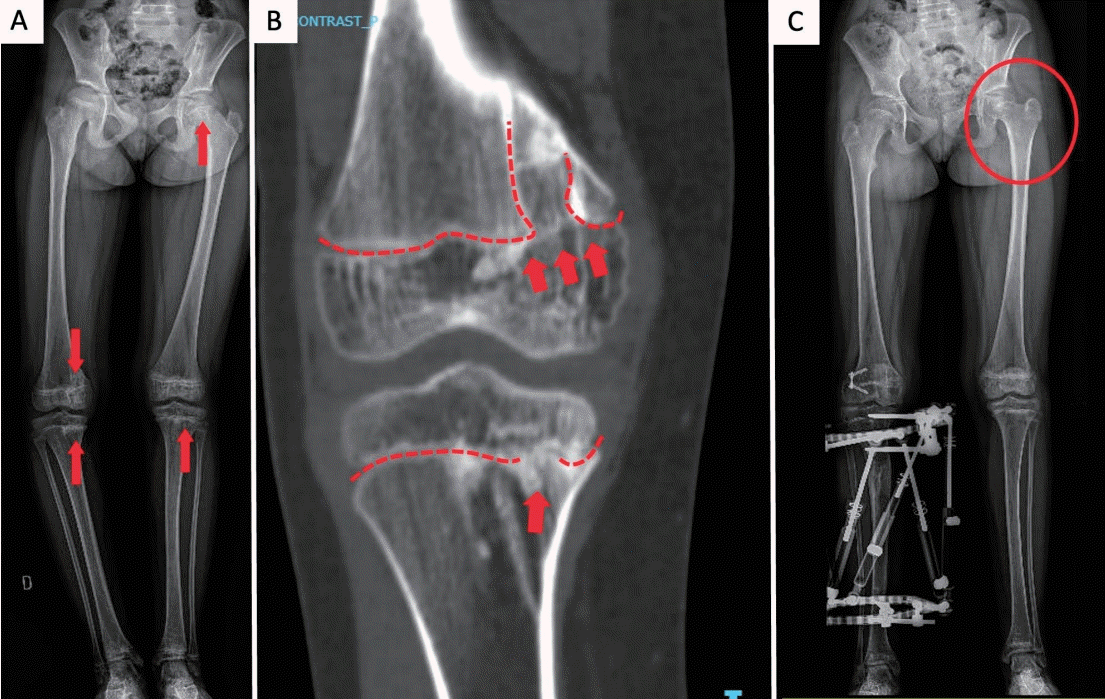

As the patient grew, scoliosis became evident, and she developed right-sided genu varum. Radiographs demonstrated asymmetric physeal bone bridges across the medial distal femoral and proximal tibial physes on the right, with additional bridges across the left tibial physis and the left femoral head physis; the latter was associated with coxa breva (Figs. 2A and B). These bridges produced focal growth arrest rather than diffuse physeal involvement.

Radiographic features and management. (A) Lower-limb radiograph showing osseous bridges across the right medial distal femoral and proximal tibial physes (genu varum), left tibial physis, and left femoral head physis (coxa breva) (arrows). (B) Detail of medial femoral/tibial bridges; the dashed lines indicate physes interrupted by bridges (arrows). (C) Postoperative radiograph showing lateral distal femoral hemiepiphysiodesis and tibial external fixator for medial distraction osteogenesis; the circle marks the left coxa breva.

Orthopedic correction comprised lateral distal femoral hemiepiphysiodesis to restrain lateral growth and tibial distraction osteogenesis with an external fixator to restore medial length and alignment, achieving correction of genu varum and limb-length equality (Fig. 2C).